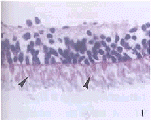

图1 改良的准分子激光切削法获取的感光细胞组织片,箭头示完好的内外节段(HE×400) 图2 酶分层消化法获取的感光细胞组织片,箭头示较好的外节段(HE×400) 图3 常规明胶粘固的视网膜经激光切削后的感光细胞组织片,箭头示受损的外节段(HE×400) Fig.1 Photoreceptor sheets ablated by modified excimer laser

surgery arrows indicate photoreceptors with perfect inner and outer segment(HE×400) Fig.2 Photoreceptor sheets obtained by enzyme gradation digestion

由改良的准分子激光切削法和酶分层消化法获取的视网膜组织片经苏木素-伊红染色,并与正常的视网膜标本进行对照,结果均显示为单一的纯感光细胞层并具有内外节段,可用于视网膜纯感光细胞移植研究中。改良的准分子激光切削法能精确地切削去除视网膜内8层结构,只剩下完整的外核层即感光细胞胞核所在(图1),且锥杆细胞的内外节段保持良好(箭头所示)。本研究发现人、兔、猪和鼠眼材料来源的视网膜所用的激光切削参数都相同,视网膜后极部血管分布区的切削深度为63~65μm,这与Dowling[3]报道的大多数脊椎动物视网膜的结构和厚度都基本一致的理论相符,切削参数的确定也极大方便日后进行多种种属视网膜感光细胞移植供体的取材。酶分层消化法虽不能精确地将视网膜消化至只剩完整的外核层,但也可得数量较多的感光细胞(图2),也仍具较好的内外节段(箭头所示)。各种材料来源的视网膜所用酶的浓度和作用时间也都相同,但胚眼组织消化时间则可短些,因为胚胎组织细胞间的连接较成年组织的疏松。而所用明胶粘贴固定的视网膜经激光切削后同样可获得纯感光细胞层(图3),但其内外节段因接触粘附在明胶中,已模糊不清,无法辨认,明显受损(箭头所示)。(图1~3见237页)